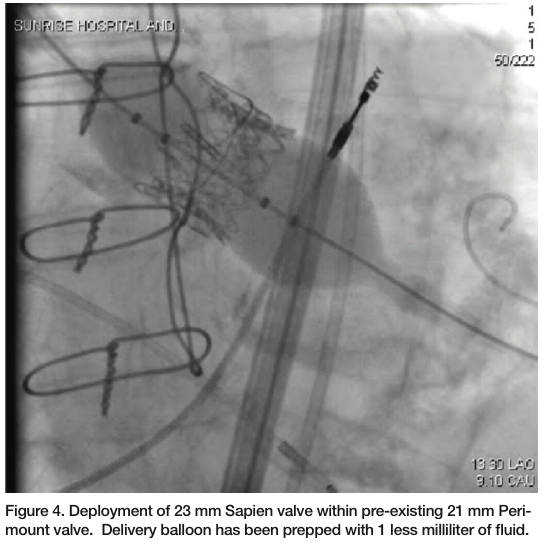

Peripheral access was gained with retroperitoneal exposure of the left common iliac artery and the attachment of a 10 mm graft conduit, as the trans-apical approach to TAVR has not yet been FDA approved for utilization in the commercial setting. Subsequently, a 22 French delivery system was inserted through the conduit into the thoracic aorta. Balloon aortic valvuloplasty was performed with a 20 mm Z-Med balloon (NuMED). A 23 mm Sapien valve (Edwards Lifesciences) was prepped in the standard fashion. However, 1

milliliter (mL) was taken out of the balloon on which the valve was mounted, because we were planning to place a 23 mm Sapien valve in the strut of a previously placed 21 mm prosthesis. The Sapien valve was then delivered through the 22 French delivery system and across the bioprosthetic aortic valve, utilizing the RetroFlex delivery system (Edwards Lifesciences). Care was made to position it so that the distal end of the Sapien valve was about 2 mm ventricular to the sewing ring of the previously placed aortic bioprosthesis (Figure 3). Under rapid pacing, the Sapien valve was deployed (Figures 4-5). Immediately post deployment, the aortic insufficiency was completely abolished, and peak velocity across the aortic valve was about 1 m/sec, with a peak velocity of about 3 m/sec at the beginning of the procedure.